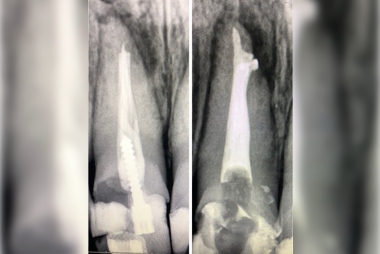

Root canal treatment, cracks and fractures in the teeth, deep decays in the teeth, cleaning, disinfecting and filling the infected tissue in the canals of the tooth with root canal filling materials as a result of the loss of vitality of the nerves and veins in the tooth is called canal treatment.